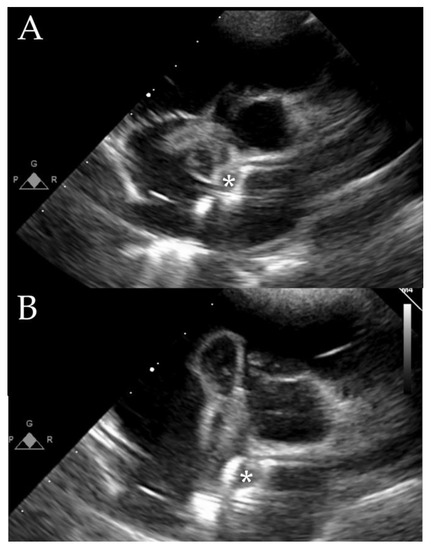

- Caiati, C.; Pollice, P.; Lepera, M.E.; Favale, S. Pacemaker Lead Endocarditis Investigated with Intracardiac Echocardiography: Factors Modulating the Size of Vegetations and Larger Vegetation Embolic Risk during Lead Extraction. Antibiotics 2019, 8, 228. [Google Scholar] [PubMed]

- Caiati, C.; Luzzi, G.; Pollice, P.; Favale, S.; Lepera, M.E. A Novel Clinical Perspective on New Masses after Lead Extraction (Ghosts) by Means of Intracardiac Echocardiography. J. Clin. Med. 2020, 9, 2571. [Google Scholar]

- Yang, Y.C.; Aung, T.T.; Khan, S.; Wase, A. Utility of Intracardiac Echocardiography to Diagnose Infective Endocarditis. J. Investig. Med. High Impact Case Rep. 2019, 7, 2075. [Google Scholar]

- Parbhoo, P.; Nell, T.; Meel, R. Assessment of pacemaker lead-related infective endocarditis with three-dimensional echocardiography and cardiac computed tomography. Cardiovasc. J. Afr. 2022, 33, 36–40. [Google Scholar] [CrossRef]